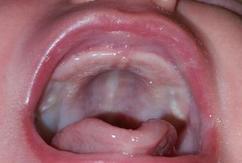

These are white spots on the roof of a baby s mouth.

Thrush or the white patches can be seen inside the cheeks on the roof of the mouth on the tongue on the gums commonly found in babies of two months and younger but could appear in older. They are usually the size of a sesame seeds. She told that the white patch could be thrush yeast infection caused by the fungus candida albicans. White patches in the mouth or small white spots in the mouth can be a sign of cancer thrush leukoplakia an std strep throat etc.

Here are the causes related symptoms and treatment for small white patches in the mouth. Regardless of cause though milk residue isn t permanent nor a reason for concern. With the peeling white mouth patches spots and bumps you can get bad breath sore gums and even pain. This can also happen if your baby has a high palate and their tongue can t reach the roof of their mouth.

They were first described by alois epstein in 1880. They generally appear along a baby s gums or along the top of the roof of the mouth. They disappear in a month or two.